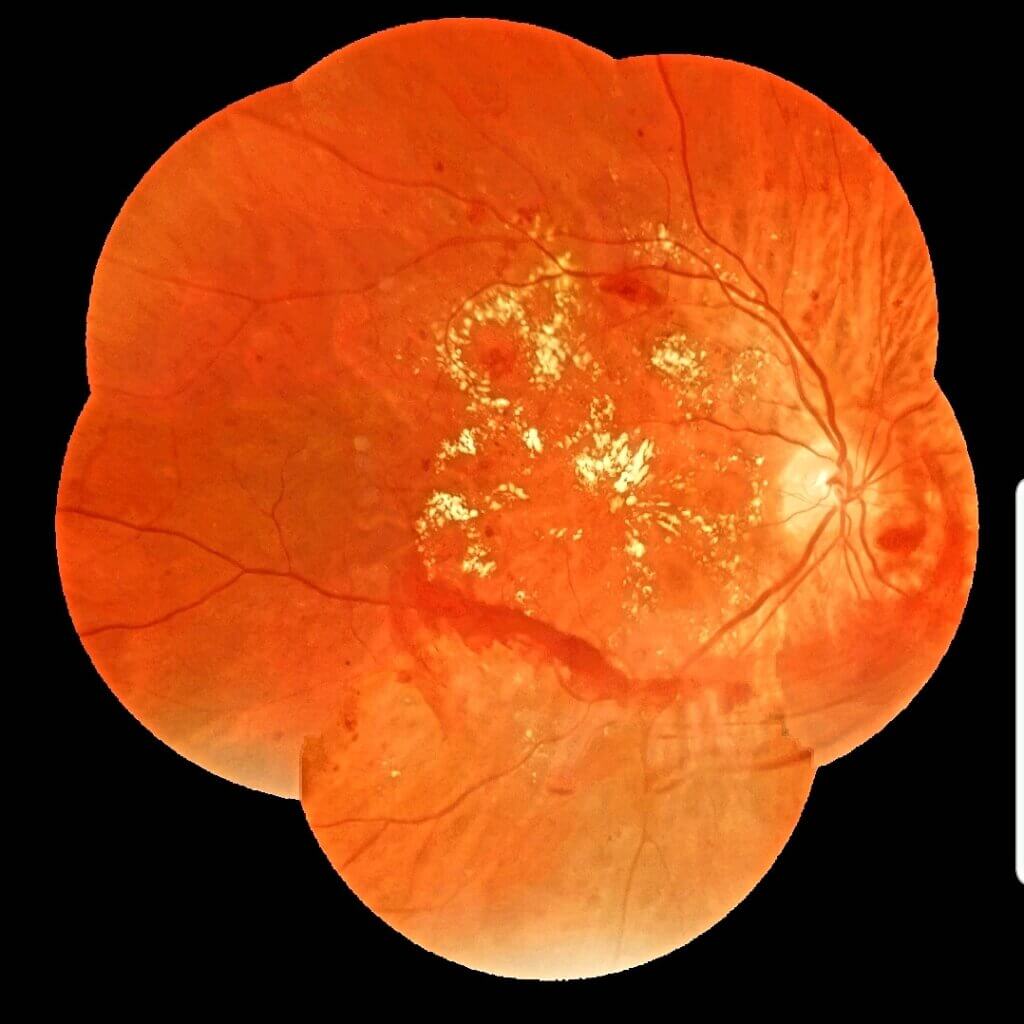

Thus, it helps diagnose of eye-related diseases, such as diabetic retinopathy, glaucoma, cataract, age-related macular degeneration (AMD), retinoblastoma, retinal detachment, retinopathy of prematurity and blindness, inter alia.

Since then, the specialist has carried out more than 500 exams, mainly to detect diabetic retinopathy. “Eyer is easy to handle and makes excellent-quality images”, he states.